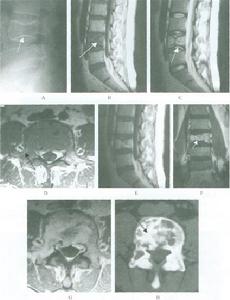

普通X線檢查中,頸椎側位片和矢狀面的斷層對Ⅰ型骨折的診斷非常有用。側位片可顯示骨折線通過樞椎椎體背側,椎體的前方大部分和寰椎一道向前移位,並伴屈曲或伸展的成角畸形,而其椎體後、下部位仍在原處,位於C3椎體上方的正常位置,斷層以片可清楚顯示骨折線及骨折塊移位的情況。開口位片和冠狀面的斷層片對Ⅱ型骨折的診斷非常有價值,可顯示樞椎側塊塌陷、寰椎側塊進入樞椎上關節面。

CT尤其是CT三維重建對了解骨折的全面信息非常重要。

MRI對軟組織的良好解析度使其在脊髓損傷中使用廣泛;同樣,在樞椎椎體骨折患者中,MRI可清楚顯示脊髓損傷和受壓的情況。

另外對於一些移位很小的樞椎椎體矢狀骨折和後緣冠狀骨折僅攝正側位X線片容易漏診,故對可疑患者應加攝張口正位和屈伸側位X線片。有學者指出,觀察樞椎椎體骨折最清晰的手段是CT薄層重建。對本病的鑑別診斷極有幫助。